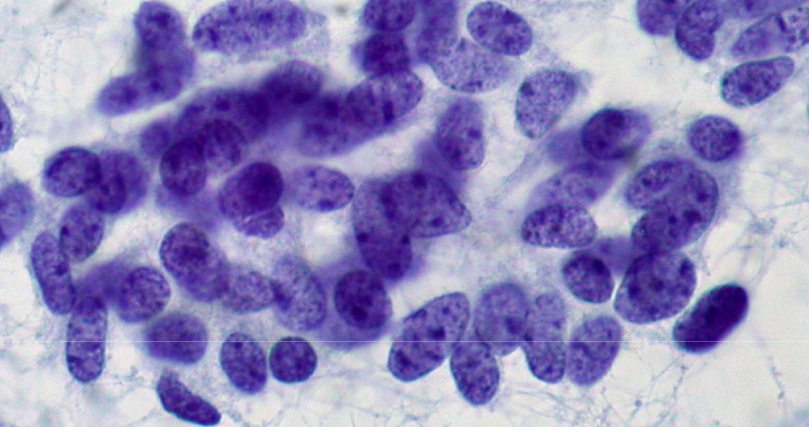

small cell carcinoma (SCLC)